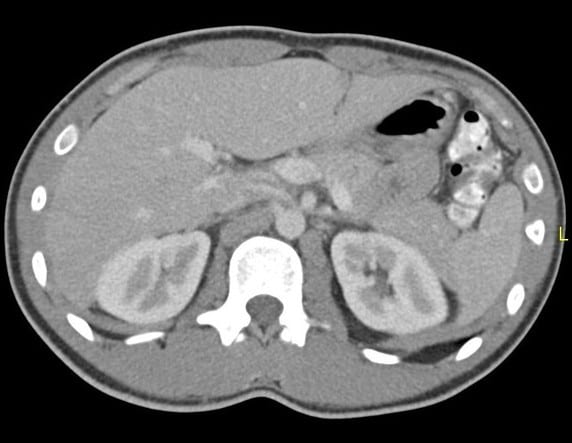

Hội chứng kẹp hạt dẻ

» Thông tin: Nam giới – 20 tuổi.

» Lâm sàng: Đau mạn sườn trái.